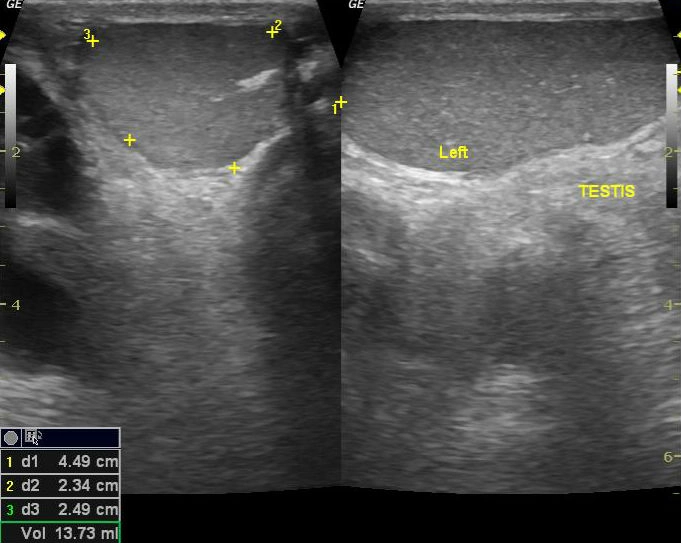

Vôi hóa bìu vô căn (Idiopathic scrotal calcinosis)

16/03/2026